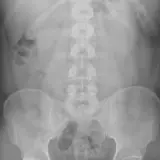

Over 2,100 interactive radiology cases, curated by radiologists for your level of training. Scroll, window, and view cases full screen — just like on PACS. Click linked findings in each writeup to jump straight to them on the image. Cases include sample reports, a focused discussion section, original illustrations, and videos.

PACSで期待されるツールを完備した完全インタラクティブな症例 — スクロール、ウィンドウ調整、ズーム、パン、計測、ROI、フルスクリーンモード。

重要な所見を症例画像上に直接ハイライトする豊富なアノテーション。症例解説内のリンクされた所見をクリックすると、スキャン上の正確な位置へジャンプできます。